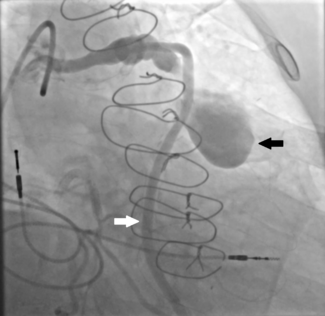

Over 5.7 million people in US and 20 million people worldwide suffer from heart failure and about half of these suffer from Heart Failure with Preserved Ejection Fraction (HFpEF). Most drug trials have shown minimal beneficial effects, and attention has turned to possible device therapy. The CORolla is an elastic device implanted in the LV through transapical approach or percutaneous approach. The device applies direct internal expansion forces distributed on the LV wall and the septum. Clinical studies are in progress. The ImCardia device is an elastic expanding device that is attached to external LV surface through off pump procedure. A study in patients admitted for AVR secondary to aortic stenosis showed trends to improvement in diastolic dysfunction after 24 months.

No devices (or drugs) have yet emerged with significantly positive impact on diastolic dysfunction. Further research with Parachute Venrtricular Positioning Devices is needed. We suggest careful assessment of diastolic outcomes in device treatment for systolic dysfunction. Alternate therapies including renal denervation, CRT and gene therapy need to be explored. Treatment of underlying causes and ultimately “Prevention” is the best therapy we have to offer our patients currently.